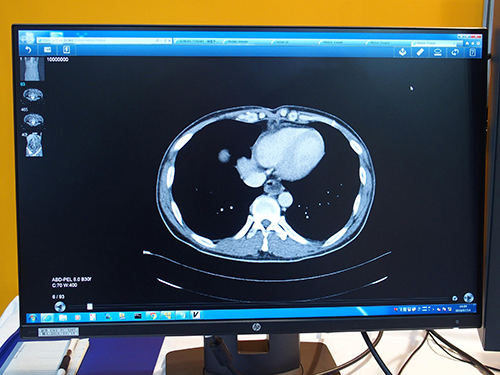

TONARIでの検査画像のビューワ表示例